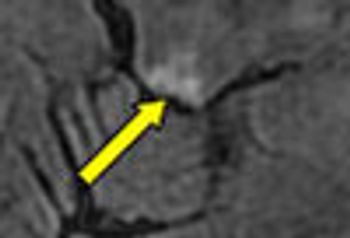

The patient, a 70-year-old man, has been having difficulty chewing and swallowing has been using his hand to hold his jaw closed while he eats; otherwise, his jaw hangs open. His speech is slightly slurred.